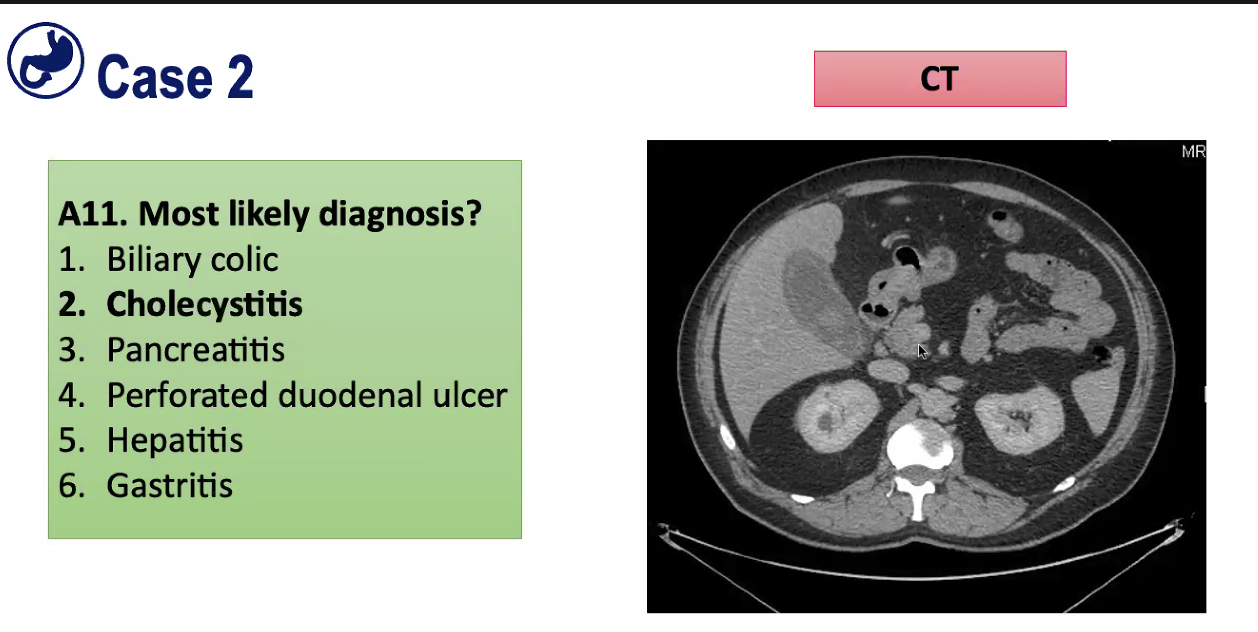

Now most likely diagnosis?

=Cholecystitis

Can see gall bladder where liver is but its slightly white around edge, opacification, consistent with inflammed gall bladder. (blood supply is enhancing)

Not pancreatitis as amylase is fine

Big difference between Cholecystitis and biliary colic. Biliary colic is crampy pain of stone trying to get out with no inflammation. Cholecystitis is usually a stone that has blocked the cystic duct, and you get pain from that as it gets infected and this is a very different pain which is constant pain which is tender.